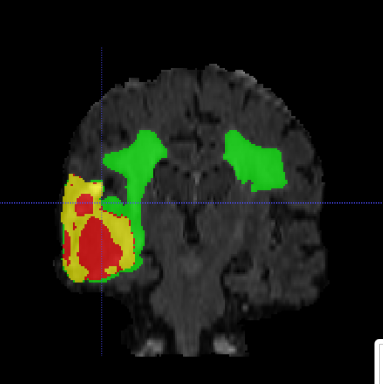

Multimodal Brain Tumor Segmentation Challenge (BraTS) aims to evaluate state-of-the-art methods for the segmentation of brain tumors by providing a 3D MRI dataset with ground truth tumor segmentation labels annotated by physicians [6, 11, 5, 3, 4]. This year, BraTS 2021 training dataset included 1251 cases, each with four 3D MRI modalities (T1, T1c, T2 and FLAIR) rigidly aligned, resampled to 1x1x1 mm isotropic resolution and skull-stripped. The input image size is 240x240x155. The data were collected from multiple institutions, using various MRI scanners. Annotations include 3 tumor subregions: the enhancing tumor, the peritumoral edema, and the necrotic and non-enhancing tumor core. The annotations were combined into 3 nested subregions: whole tumor (WT), tumor core (TC) and enhancing tumor (ET), as shown in Figure 1. Two additional datasets without the ground truth labels were provided for validation and testing. The validation dataset (219 cases) allowed multiple submissions and was designed for intermediate evaluations. The testing dataset (530 cases) will be analysed blindly using the docker submission, and is used to calculate the final challenge ranking.

Typically, the output result, even of a single model, is accurate as shown in Figure 1, however several cases still remain segmented imprecisely. Figure 2 shows an example of an incorrectly over-segmented whole tumor (WT) region, which is spilled over on the right side of the brain, most likely because the underlying MRI (Flair) has substantially higher intensity values in that region. More variability in training examples might have helped to solve the issue, or integration of anatomical knowledge of e.g. ”symmetrical highlights around ventricles are unlikely to be a tumor” , but such information is rather complicated to put inside of the network.